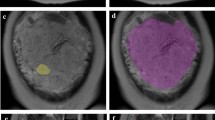

64 patients (n=41 with PAS and n= 23 without PAS) with PP who underwent MRI examination for suspicion of PAS were retrospectively selected. All MRI examinations were acquired on a 1.5 T using T2-weighted (T2w) sequences on axial, sagittal and coronal planes. Ten different manual segmentation methods were performed on sagittal placental T2-weighted images obtaining five sets of 2D regions of interest (ROIs) and five sets of 3D volumes of interest (VOIs) from each patient. In detail, ROIs and VOIs were positioned on the following areas: placental tissue, retroplacental myometrium, cervix, placenta with underneath myometrium, placenta with underneath myometrium and cervix. For feature stability testing, the same process was repeated on 30 randomly selected placental MRI examinations by two additional radiologists, working independently and blinded to the original segmentation. Radiomic features were extracted from all available ROIs and VOIs. 100 iterations of 5-fold cross-validation with nested feature selection, based on recursive feature elimination, were subsequently run on each ROI/VOI to identify the best-performing method to classify instances correctly.

Among the segmentation methods, the best performance in predicting PAS was obtained by the VOIs covering the retroplacental myometrium (Mean validation score: 0.761, standard deviation: 0.116).

Our preliminary results show that the VOI including the retroplacental myometrium using T2w images seems to be the best method when segmenting images for the development of ML radiomics predictive models to identify PAS in patients with PP.